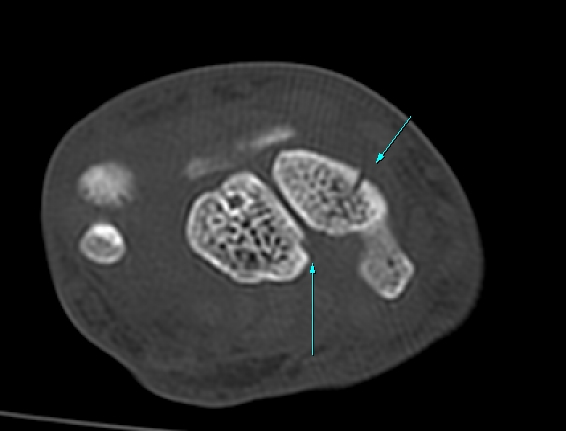

¼Õ¸ñ ¿ä°ñÃø ÁÖ»ó°ñ Á¾´Ü¸é °Ë»ç¿¡¼ ÁÖ»ó°ñ ÇÇÁú°ñ ¿¬¼Ó¼º ¼Ò½ÇÀÌ ¶Ñ·ÈÇÏ°í µ¿¹ÝµÈ ¿¬ºÎÁ¶Á÷ ºÎÁ¾ÀÌ °üÂûµÊ(»çÁø 3, 4)/

CT °Ë»ç